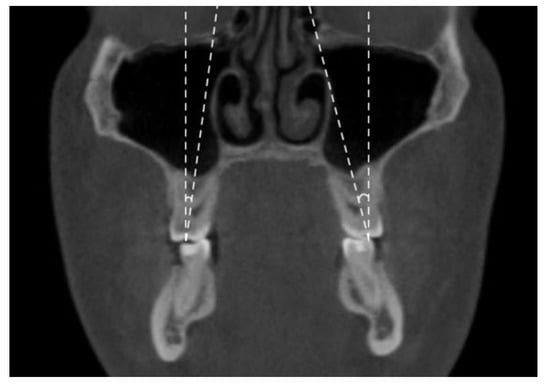

- Maxillary inter-buccal bone widths: from the right to the left points at the level of hard palate, alveolar crest and furcation (Figure 1)

- Maxillary inter-lingual bone widths: from the right to the left points at the level of alveolar crest and furcation (Figure 2)